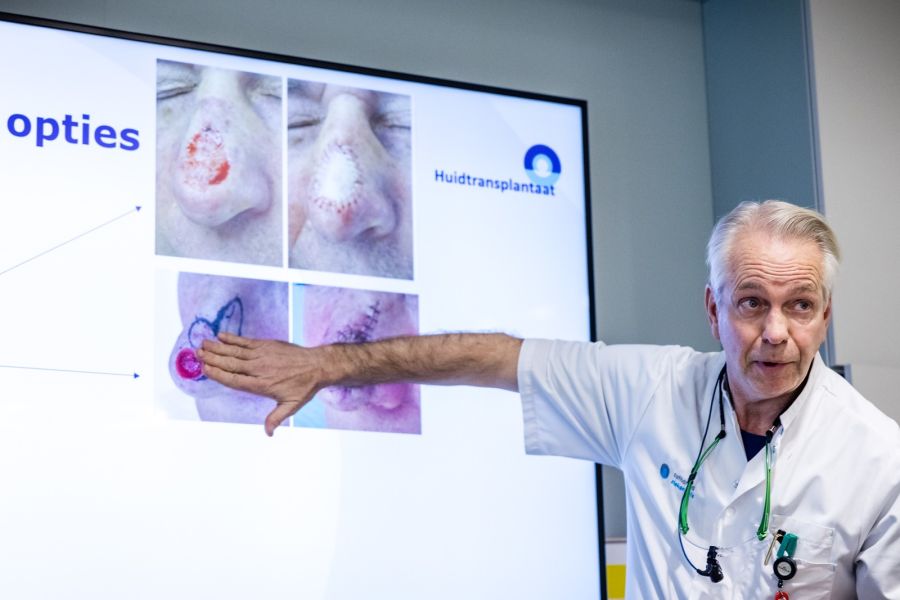

Maasstad Ziekenhuis voert eerste behandeling uit met gekweekte huid bij baby met ernstige brandwonden

mei 1, 2025

In het Brandwondencentrum van het Maasstad Ziekenhuis is voor het eerst in Nederland een baby met ernstige brandwonden behandeld met gekweekte huid afkomstig van de baby zelf. De baby, van wie 70% van het lichaamsoppervlak was verbrand, is de jongste patiënt ooit die deze DenovoSkin™-behandeling heeft ondergaan, buiten een onderzoekssetting. Eigen huid versnelt herstel en geeft […]